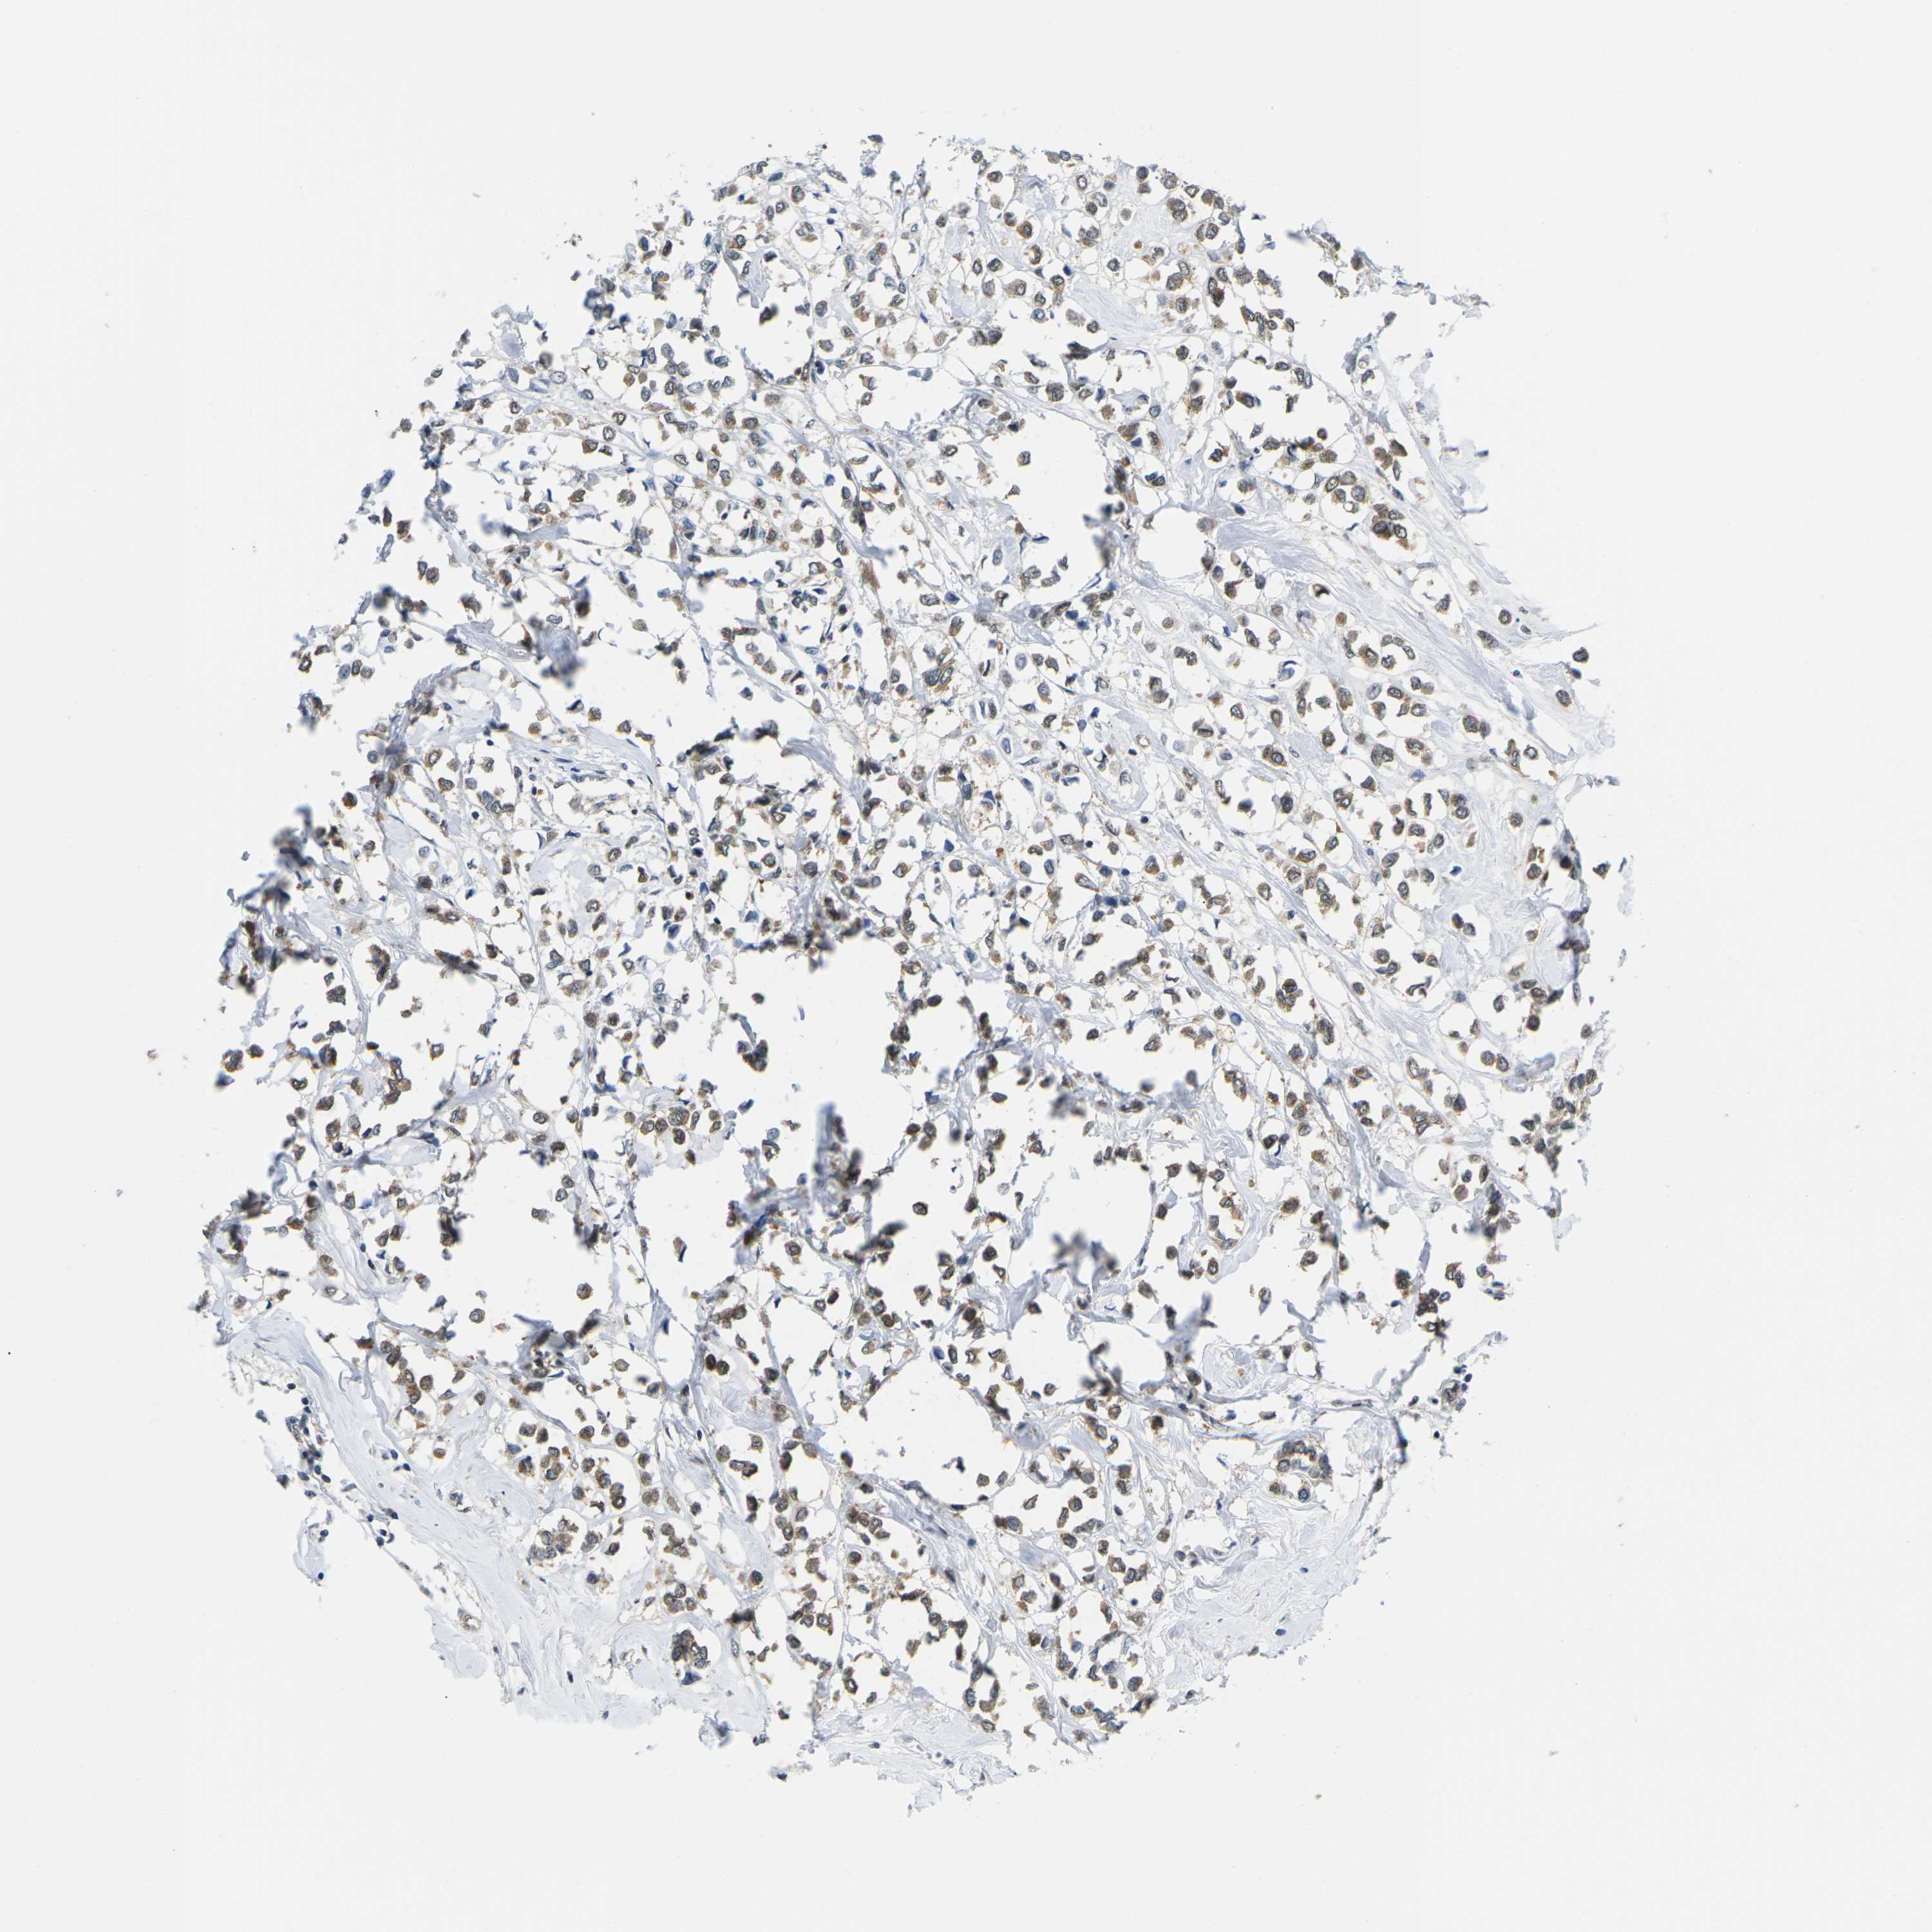

CANCER BREAST CANCER Show tissue menu

BRCA TCGA BRCA VALIDATION PROTEIN EXPRESSION